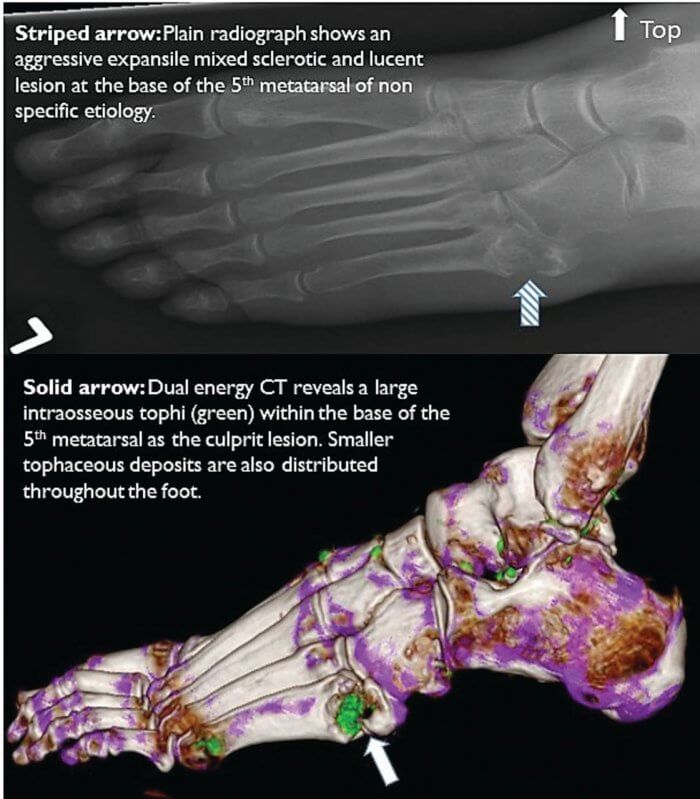

Now that technology allows us to see tophi growing into cartilage, tendons, and bones, we can see it is not wise. I’ve added some more important 2014 information to this 2010 article about early detection of joint damage from new gout scanning technology. First let us see how this technology shows early tophi leading to bone erosion and severe, painful, joint damage.

It has been a few years since improvements in scanning techniques allowed us to view what is happening inside joints. Over 3 years ago, I quoted from Dalbeth [1]:

There is a strong relationship between bone erosion and the presence of intraosseous tophus. These results strongly implicate tophus infiltration into bone as the dominant mechanism for development of bone erosion and joint damage in gout.

A significant part of Dalbeth’s, and related research, is the observation that DECT reveals urate deposits much more effectively than any other technique, to the point that joints often show uric acid deposits prior to any physical or inflammatory indication of gout.